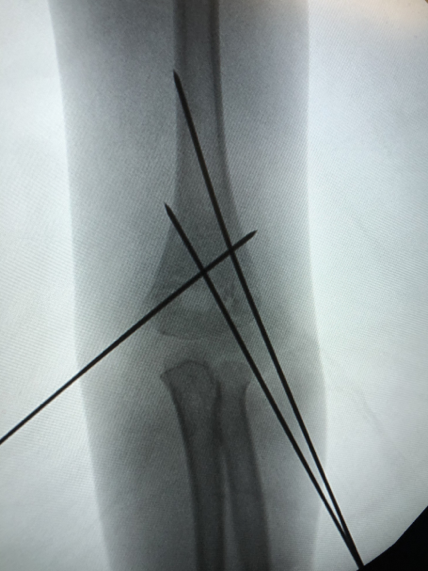

▲肱骨髁上骨折X线平片

小儿骨科康映泉副主任医师接诊后确诊是“肱骨髁上骨折”,骨折完全移位,所幸没有血管神经损伤,但仍需要手术治疗。康映泉副主任医师应用最新治疗手段,即超声引导骨折复位技术,大大降低术中辐射暴露,成功为小晨施行骨折闭合复位内固定术,术中没有伤口,针尾留置皮肤外面,待1个月后骨折愈合即可门诊拔除,无需住院或麻醉,看着无大碍的孩子,小晨爸爸悬着的心终于放下。

▲超声引导下骨折闭合复位钢针内固定及术后外观照

康映泉副主任医师介绍,自去年开始,我院小儿骨科已成功开展数十例超声引导下儿童四肢骨折微创复位、内固定,包括肱骨髁上骨折、肱骨外髁骨折、尺桡骨骨折、胫腓骨骨折等,应用超声引导技术,极大降低术中辐射暴露,特别是对于儿童患者,低辐射手术对其生长发育具有至关重要的作用。

▲超声引导下骨折闭合复位钢针内固定术